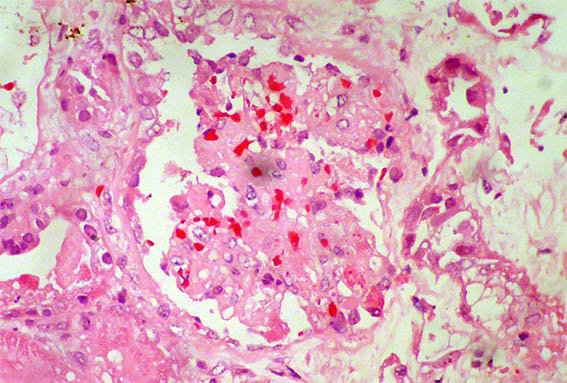

Figure 1. H&E, X100.